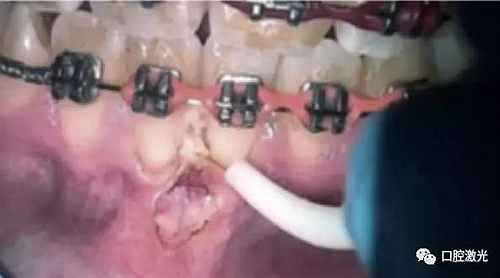

半導體口腔激光活檢術(shù)即可效果